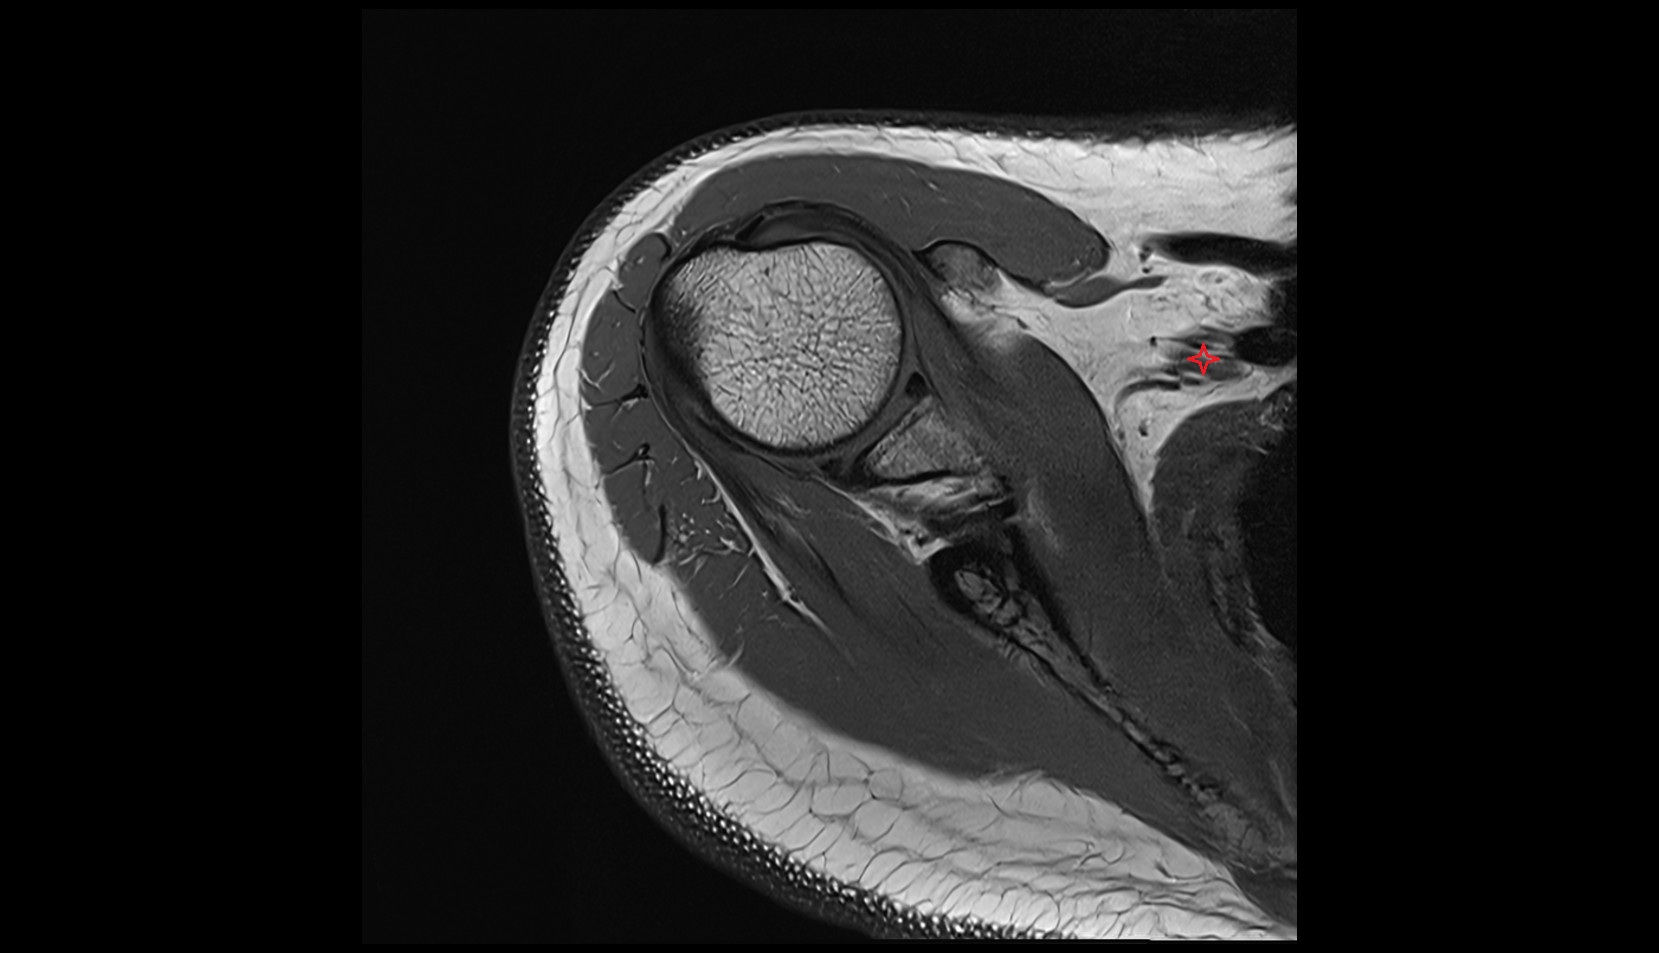

- Shoulder joint (glenohumeral joint)